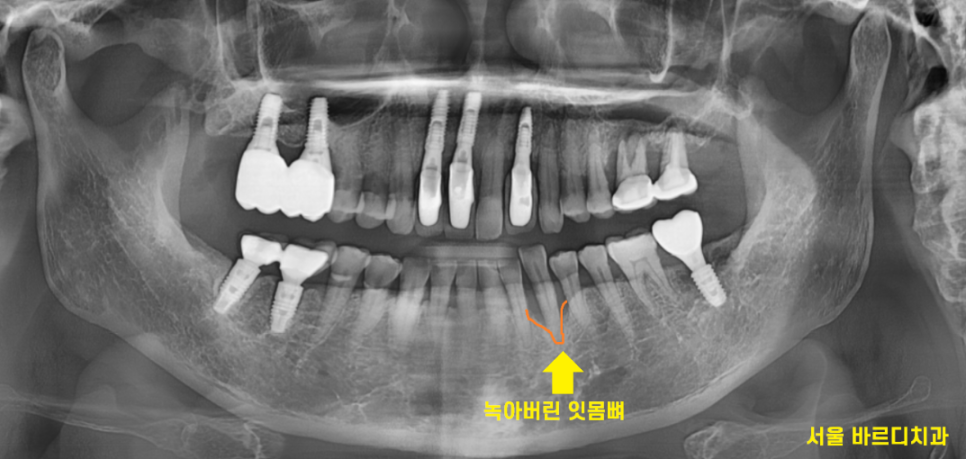

24.04.16

x-ray 상에서도 잇몸이 많이 녹아있네요ㅠㅠ

잇몸뼈가 많이 녹아

치아 뿌리만 겨우 붙잡고 있습니다.

붙잡고 있는게 얼마 없어

식사할때마다 흔들렸을꺼고

많이 불편하셨겠어요~